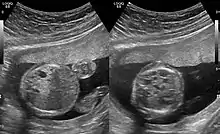

CPAMs are often identified during routine prenatal ultrasonography. Identifying characteristics on the sonogram include: an echogenic (bright) mass appearing in the chest of the fetus, displacement of the heart from its normal position, a flat or everted (pushed downward) diaphragm, or the absence of visible lung tissue.

Congenital pulmonary airway malformation in a fetus, ultrasound at 19 weeks - transverse. Stomach on left image; heart on right image: displaced to right by cystic mass

The earliest point at which a CPAM can be detected is by prenatal ultrasound. The classic description is of an echogenic lung mass that gradually disappears over subsequent ultrasounds. The disappearance is due to the malformation becoming filled with fluid over the course of the gestation, allowing the ultrasound waves to penetrate it more easily and rendering it invisible on sonographic imaging. When a CPAM is rapidly growing, either solid or with a dominant cyst, they have a higher incidence of developing venous outflow obstruction, cardiac failure and ultimately hydrops fetalis. If hydrops is not present, the fetus has a 95% chance of survival. When hydrops is present, risk of fetal demise is much greater without in utero surgery to correct the pathophysiology. The greatest period of growth is during the end of the second trimester, between 20–26 weeks.